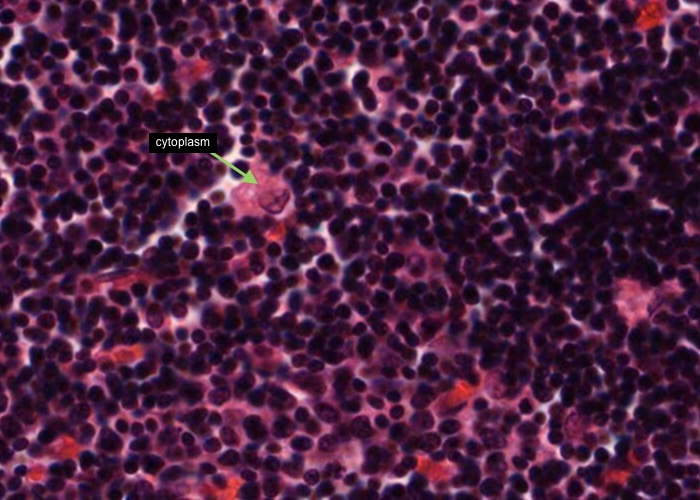

Each type II epithelioreticular cell has a pale-stained nucleus and lies within the parenchyma of the cortex. Their cytoplasmic extensions join (via maculae adherents) with other type II cells and they compartmentalise the developing T- cells and also participate in their development.